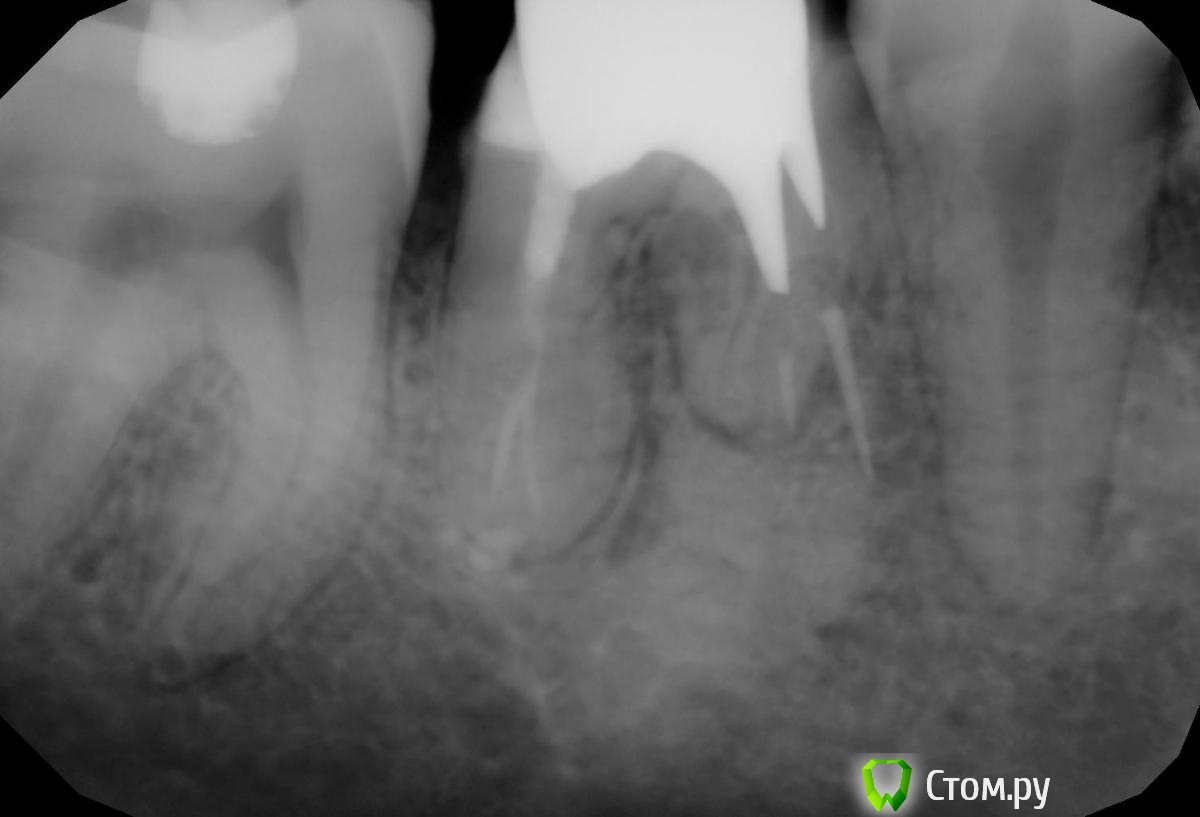

TAB497 Опубликовано 10 января, 2014 Поделиться Опубликовано 10 января, 2014 добрый день!огромная просьба проконсультируйте по моему- насколько опасна межкоррневая киста 46 зуба?обратилась в клинику, чтобы закрыть 46 зуб металло-керамической коронкой, т.к. сам зуб уже давно не живой и в виду сильной истираемости и неправильного (как сказали врачи) лечения в детсве натуральная коронковая часть зуба была истерта практически до десны. мне сделали панорамный снимок челюстей и направили на перепломбирование каналов. Перепломбировать удалось только ождин канал и ещё ождин частично, третий пройти вообще не удалось. До перелечивания каналов зуб н еболел и только изредка чувствовались по середине зуба покалыювающие боли при жевании твердой пищи. НО после перелечивания каналов, когда прошло действие замомрозки, я почувствовала лискомфорт от временной пломбы и жевать на этой стороне уже мне могла, т.ку. это вызывало боли. На второй день обратилась к врачу, мне сказали, что такое бывет, когда вмешиваются в такой сложный зуб. Но тем не менее тут же направили на слепок для металлической вкладки, укрепляющей зуб для дальнейшей установки коронки. на момент установки этой вкладки зуб продолжал болеть при жевании, в свободном состоянии никаких жалоб не было, но несмотря на мои сообщения о болях, мне поставить разборную вкладку и назначили физитерапию лазером на неделю, при этом запретили жевать на зубе, раз возникают боли. Показалось ,что боли уменьшились, т.к. давление на зуб сократилось, мне поставили временную коронку, но снова после вернувшегося режима жевания на этом зубе, боли вернулись и даже чуть припухла щека(то ли от неаккуратно обработанной коронки то ли от болей у корня зуба) коронку мне сняли, жевать перестала, примерно через неделю припухлость щеки и десны ушла, но я тогда же услышала вердикт - зуб лечению и восстановлению не подлежит, только удаление!!! для меня это был шок...мне всего 26 лет и уже приходится удалять жевательный зуб, после обращения с просьбой восстановления..!!! все это ещё совсем не кстати, т.к. я планировала расшиерние семьи, рождение ребенка в ближайшее время (потому и стала проверять и залечивать зубы). Теперь мне должы удалить этот зуб (снимок прикреплен) НО никто не объясняет,что это за мутные образования около правого корня, я начиталась интеренет-статей об угрозе остеомиелита в случае запущенной кисты, и что это заболевание может развиться за месяц, а уже двв месяца прошло с момента появления этих болей и попыток их лечить..в итоге нахожусь в предпаническом состоянии. Перед НГ не успела удалить, а сейчас ловлю себя на мысли, что боли не такие сильные при жевательном давлении на зуб, если разжевывать что-то жесткое, то чувствуется зуб, а если мягкую пищу, то, в общем- то и нет жалоб..теперь сомневаюсь, а стоит ли сейчас удалять? зуб покрыт временной коронкой, может, и могу ещё пожить с этим зубом? нет ли опастности заражения организма от этой кисты? можно ли оставить этот зуб на время беременности и вскармливания ребенка, т.е. на период порядка 2 лет? или лучше все-таки удалить? Огромная просьба извинить за, возможно, ненужные подробности, но поскольку абсолютной ясности после общения с лечащим врачом нет, я очень переживаю из-за смутных ощещений, то болел, то теперь не болит..без жевательного зуба тоже не очень приятно жить 2 года.. Очень жду ответов и моральной поддержки ) заранее огромное спасибо за внимание и участие! Ссылка на комментарий

TAB497 Опубликовано 14 января, 2014 Автор Поделиться Опубликовано 14 января, 2014 Большое спасибо всем за ответы! очень, конечно, печально терять зуб, но, очевидно, иного выхода нет.. Извините, пожалуйста, за назойливость, но подскажите, если несложно,ещё один момент - верный ли поставлен диагноз "межкорневая киста" или все-таки это какое-то воспаление от неправильно залеченного канала? было ещё предположение, что при проходе канала был пробит корень.. что же все-таки является наиболее вероятной причиной потери зуба, судя по снимку? И как быть после удаления? дело в том, что имплантация займет порядка 8-9 месяцев, т.к. пока зарастет кость после удаления примерно 3-4 месяца, потом приживление импланта, еще до полугода. Можно ли проходить без импланта после удаления около двух лет? Я читала, что это нежелательно, т.к. может атрафироваться костная ткань, но если вдруг по личным обстоятельствам (беременность и грудное вскармливание) не получится поставить имплант, могу ли я спокойно походить этот период с временным протезом "бабочка", например?? Ссылка на комментарий